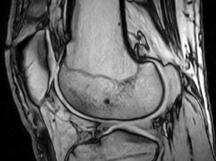

Risonanza Magnetica

Apparecchiatura

per risonanza magnetica

La Risonanza Magnetica (di seguito anche RM) è

un importante tipo di spettrografia, in cui le onde elettromagnetiche che

interagiscono con la materia sono onde radio di bassa frequenza e

quindi di energia molto piccola, essa presenta due tipi di applicazione, il

primo tipo di applicazione della RM, noto come tomografia a risonanza magnetica fornisce immagini bi e

tridimensionali di sezioni del corpo umano e permette di ottenere informazioni

diagnostiche, il secondo tipo di applicazione, invece, esegue studi di

carattere microscopico su organi o parti sezionate di organismi viventi e

cellule in situ e in vivo.